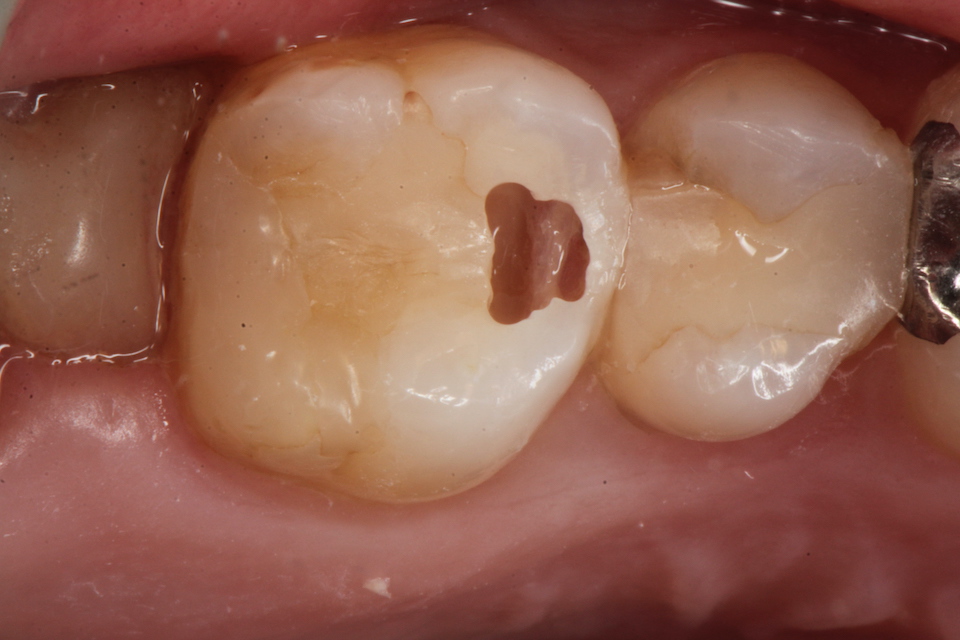

下顎7番の頬側歯茎部カリエスの原因 2025.06.04